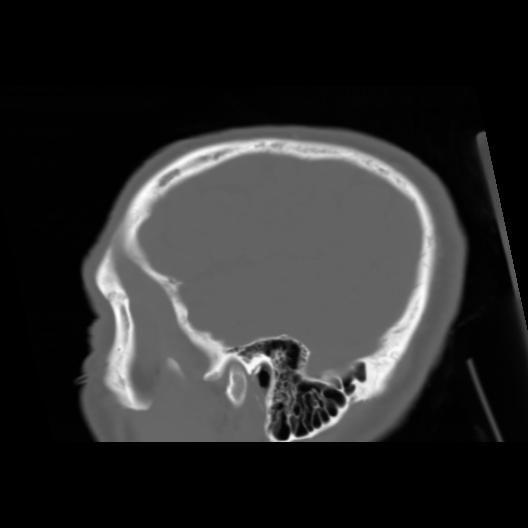

6 CEREBRO,,Sagittal,3.000,CEREBRO,Sagittal,